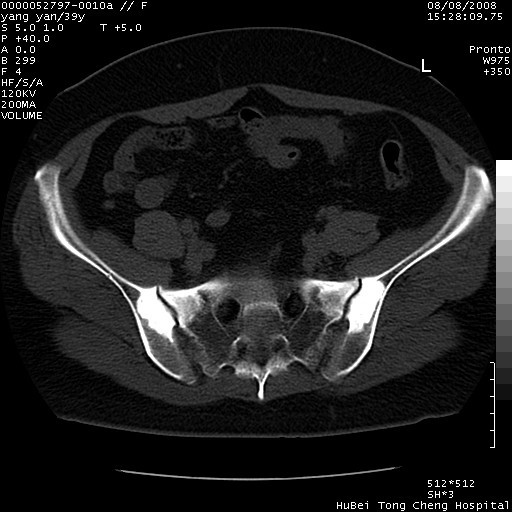

患者 女,39岁。因外伤检查,偶然发现。

典型!双侧骶髂关节致密性骨炎。

典型!病变主要累及双侧髂骨。常见于育龄期妇女。

致密性骨炎,一般不跨越关节面,可是这个骶骨关节面也有硬化。

髂骨致密性骨炎系一种以骨质硬化为特点的非特异性炎症,有高度致密的骨硬化现象,尤其以髂骨下2/3更为明显,但关节间隙则无改变。因位于骶髂关节,且该关节症状明显,故又称之为“骶髂关节致密性骨炎”。 本病90%以上为中年女性,以妊娠后期、尤其分娩后为多见,亦可见于尿路或女性附件慢性感染后,或盆腔内其他感染。此外,臀骶部的外伤亦可诱发或引起本病。  妊娠、分娩及外伤均可引起骶髂关节韧带的撕裂而易使局部的血供受阻。因此早期局部呈现充血、水肿及渗出增加等,渐而局部出现增生与变性反应,随着胶原纤维的致密化而向硬化演变;血管形成厚壁血管,易闭塞而引起髂骨耳状面处缺血和缺氧,骨质呈现硬化性改变,以致手术时局部出血较少。骶髂关节囊壁显示纤维增生、弹性降低及松动样改变。继发于盆腔内炎症者亦出现相类似的病理改变,可能系细菌内毒素作用所致。